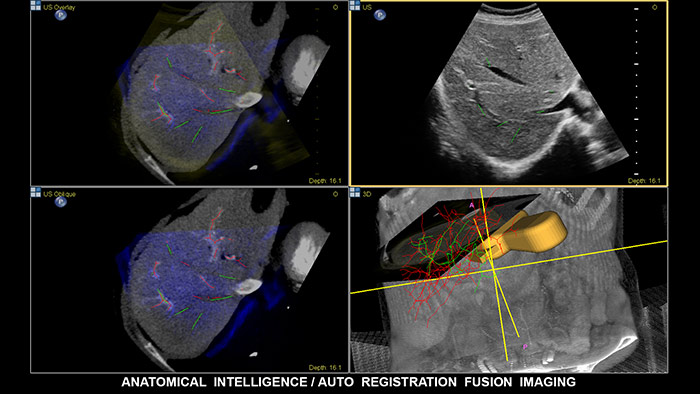

A fusão de imagens combina as vantagens inerentes da imagiologia multimodalidade diretamente no ultrassom utilizando a monitorização eletromagnética. Ao combinar TAC/RM/PET com a ultrassom e a posição do paciente em tempo real, o médico tem acesso a uma poderosa ferramenta de diagnóstico, ao mesmo tempo que limita a radiação, já que são necessários menos exames de compatibilidade, maximizando o fluxo de atendimento a pacientes do departamento. A ultrassomanatomicamente inteligente (AIUS) exclusiva do EPIQ inclui a fusão de imagens com um registo automático dos volumes de TAC/RM e de ultrassom, num décimo do tempo de alinhamento padrão. A navegação da agulha é uma ferramenta de melhoria do desempenho para casos de intervenções difíceis no fígado e está comprovado que melhora o fluxo de trabalho e reduz a exposição à radiação ao utilizar menos exames de confirmação. O EPIQ da Philips possui um conjunto completo de soluções que inclui o CIVCO eTrax™, o guia de agulha adaptativo da Philips e os guias de agulha coaxiais da Philips. Graças à ampla compatibilidade com dispositivos de biópsia e ablação, o médico tem liberdade pode escolher as melhores ferramentas para o procedimento, consoante o nível de complexidade.

Tome decisões com confiança, mesmo em casos de diagnósticos difíceis, com as capacidades de fusão de imagens e navegação da agulha da Philips. O fluxo de trabalho simplificado permite aos médicos conseguirem uma fusão rápida e eficaz de TAC/RM/PET com ultrassom em tempo real, enquanto a navegação da agulha ajuda durante biópsias de lesões pequenas e de difícil acesso.